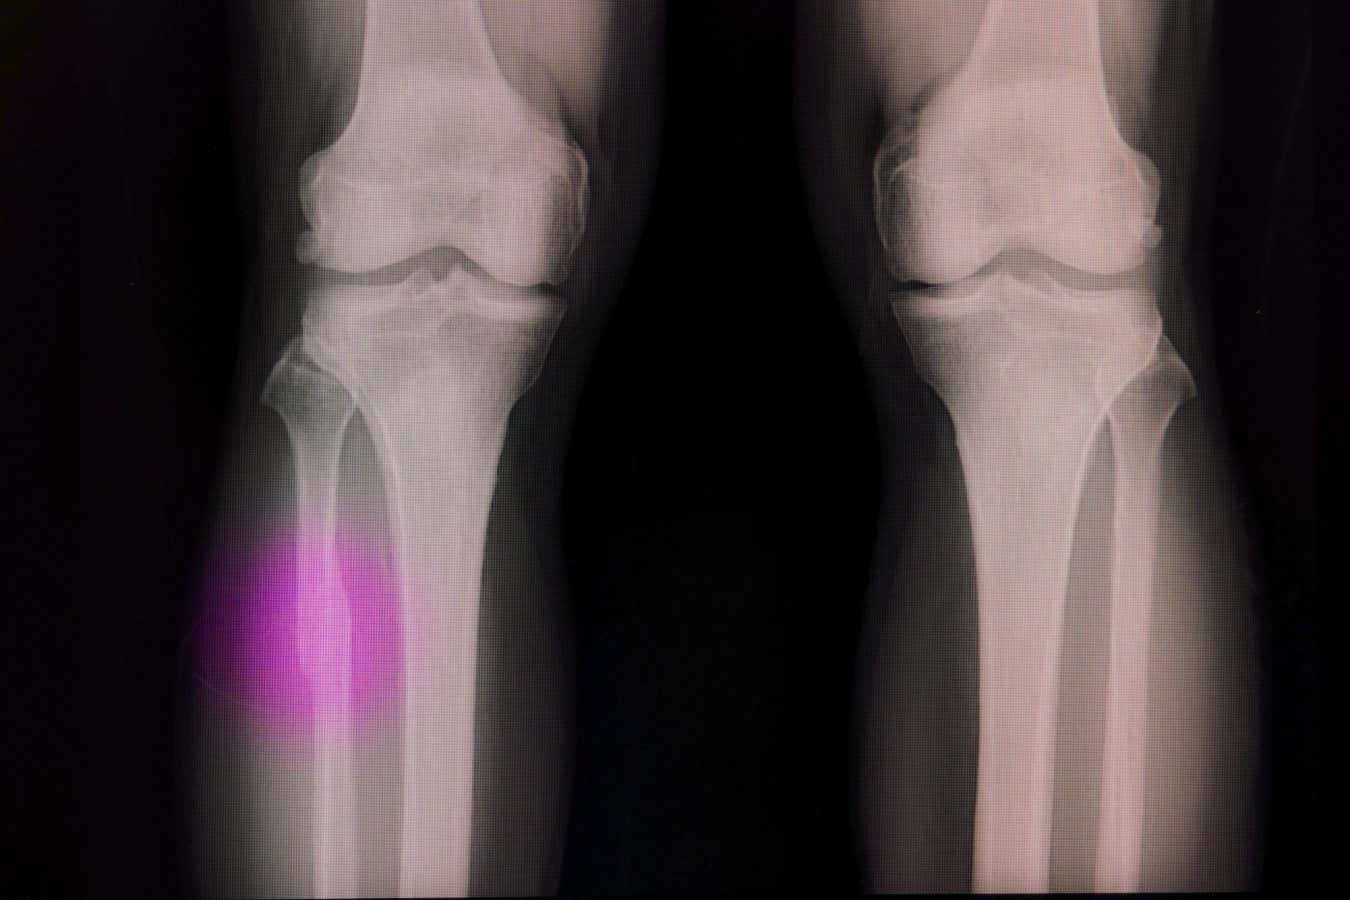

Broken bones often need a material to fill the void

Sopone Nawoot/Alamy

While bones can often heal themselves after minor injuries, serious trauma or tumor removal may leave cavities that require a synthetic plug to stimulate bone cell growth.